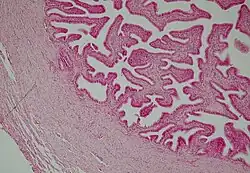

6. Tecido conjuntivo denso não modelado do esôfago

O tecido conjuntivo frouxo suporta estruturas normalmente sujeitas a pressão e atritos pequenos, sendo um tecido muito comum que preenche espaços entre grupos de células musculares, suporta células epiteliais e forma camadas em tomo dos vasos sanguíneos. É também encontrado nas papilas da derme, na hipoderme, nas membranas serosas que revestem as cavidades peritoneais e pleurais e nas glândulas. As células mais numerosas são os fibroblastos e macrófagos, mas todos os outros tipos celulares do tecido conjuntivo também estão presentes, além de fibras dos sistemas colágeno e elástico. Ele tem uma consistência delicada, é flexível, bem vascularizado e não muito resistente a trações.

Já o tecido conjuntivo denso é adaptado para oferecer resistência e proteção aos tecidos. É formado pelos mesmos componentes encontrados no tecido conjuntivo frouxo, entretanto, existem menos células e uma clara predominância de fibras colágenas. Ele é menos flexível e mais resistente à tensão que o tecido conjuntivo frouxo.

Quando as fibras colágenas são organizadas em feixes sem uma orientação definida, o tecido chama-se denso não modelado. Neste tecido, as fibras formam uma trama tridimensional, o que lhes confere certa resistência às trações exercidas em qualquer direção. Este tipo de tecido é encontrado, por exemplo, na derme profunda da pele.